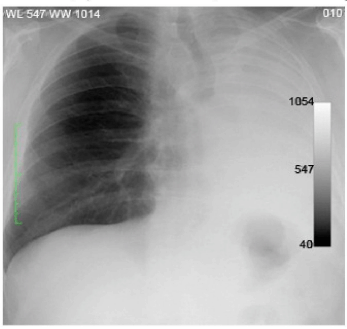

Paciente do sexo masculino, 70 anos, chegou ao pronto-socorro com dor torácica acompanhada de tosse e dificuldade para respirar. O médico que o atendeu, após o exame clínico, solicitou uma radiografia de tórax (abaixo).

A partir dos dados apresentados, assinale a alternativa que representa o achado radiológico.